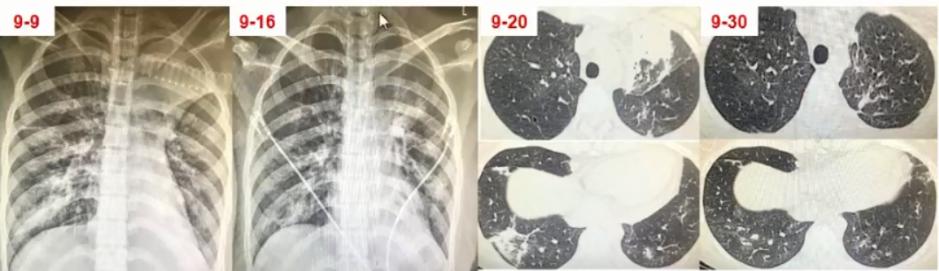

图8 患者入院当日胸部CT。左上肺大面积实变,右上肺斑片影,出现胸腔积液

入院第1日:痰培养无菌生长;痰涂片:少量G-球菌,未见真菌;血培养:5天无菌生长(普通+厌氧);GM抗原:小于0.25μg/L;G试验:96.5pg/ml

入院第2日:BALF-mNGS:肺炎支原体;BAL涂片:未找到细菌真菌、未找到抗酸菌

入院第9日肺炎支原体抗体:>1:1280

①转归

美罗培南+米诺环素治疗48小时后退热;住院治疗第5天撤机拔管;住院治疗第10天停用美罗培南;米诺环素疗程共30天;住院34天出院。